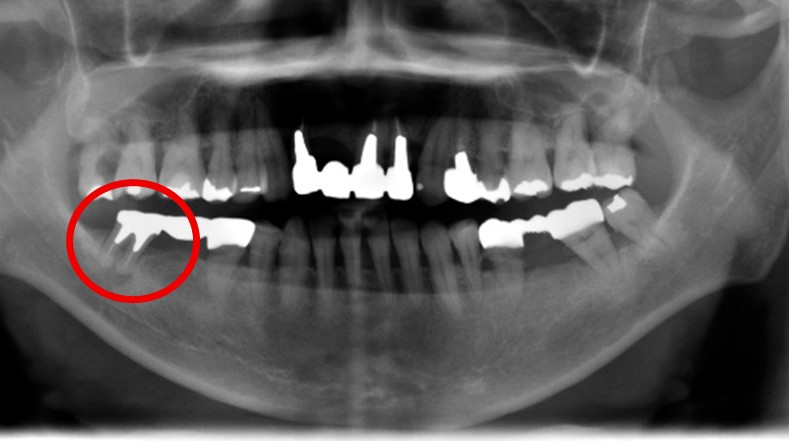

男性 Nさん 70代 (インプラント)

主訴

右下奥の歯が、グラグラして噛むと痛い。

治療内容

歯根の周りの骨が全く無い状態でしたので、保存することができず抜歯しました。3本歯がないところに2本インプラントを埋入しました。

所感

抜歯後、歯がなくなったところを補う方法には、部分入れ歯とインプラントがあります。この症例の場合、右下以外ほとんど歯が残っていますので、もし部分入れ歯にした場合、入れ歯のところで他のところと同じ感覚で噛むことができないので、慣れることが大変です。また部分入れ歯の支えになっている歯に負担がかかりますので、今後さらに歯を失う可能性が大きくなります。インプラントは、自分の歯と同じ感覚で噛むことができ、単独で植立していますので他の歯に負担がかかることがありませんので、更に歯を失うことを防ぎます。

インプラント2本:¥363,000×2本=¥726,000(税込)

ポンティック1本:¥115,500(税込)

合計:¥841,500(税込)

Before

※赤丸を抜歯しました。

After